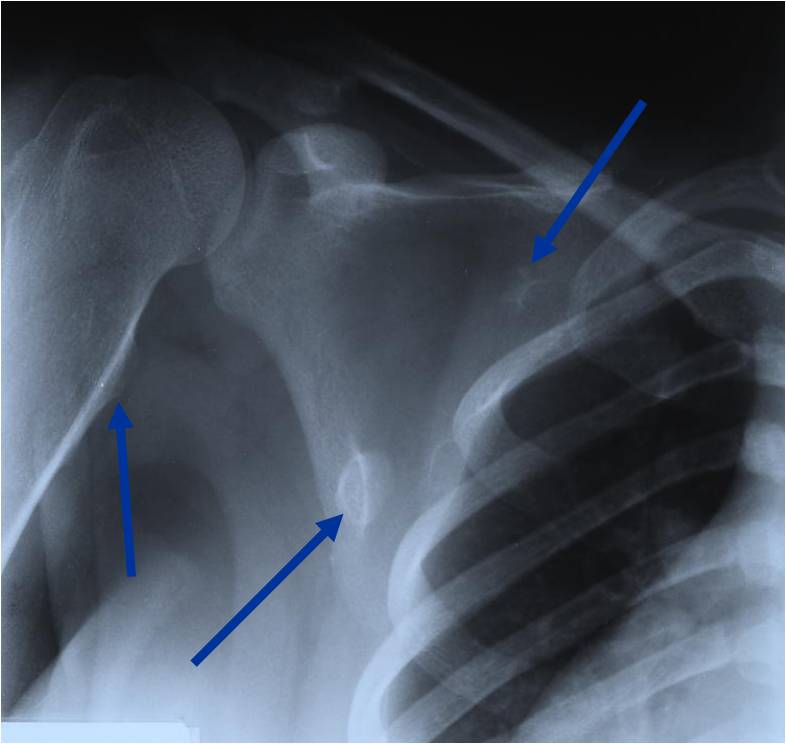

Plain X-ray: Secondary Chondrosarcoma of Proximal Femur

MRI: Secondary Chondrosarcoma of Proximal Femur: Thick Cartilage Cap (>2cm)

Osteochondroma Vs. Secondary Chondrosarcoma

The cartilaginous cap deserves the most attention when differentiating a benign osteochondroma from a secondary chondrosarcoma that arose from a pre-existing osteochondroma

In adults, the cartilaginous cap regresses and becomes thin due to enchondral ossificastion of the majority of the cap.

Malignant transformation is suggested by:

- Cartilaginous cap thickness greater than 2cm

- Cortical destruction

- Backgrowth of the cartilaginous cap into the stalk or medullary canal

- Lysis of calcifications in cap